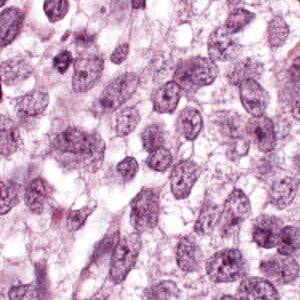

As an essential part of digital pathology, histopathology image analysis is playing increasingly important role in cancer diagnosis, which can provide direct and reliable evidence to diagnose the grade and type of cancer. This paper deals with nuclei segmentation, an important step in histopathological image analysis. The purpose of nuclei semgentation is not only counting the number of nuclei but also obtaining the detailed information of each nucleus. So unlike nuclei detection, here the outputs are the contour of each nucleus instead of only the position of their central points. Hence we can exactly extract each nucleus from the image and make it available for further analysis. For example, the features of the individual nucleus and the distribution of nuclei clusters can be used to grade and classify status of breast cancers [3, 4]. Because of appearance variation such as color, shape, and texture, nuclei segmentation from histopathological images could be very challenging, as illustrated in Fig.1, in which it is very challenging even for human to recognize and segment all nuclei within the images. Fig.1(a) and Fig.1(b) illustrate two histopathological images from different organs. Fig.1(c) and Fig.1(d) are two histopathological images from same organ but have different cancer grade.